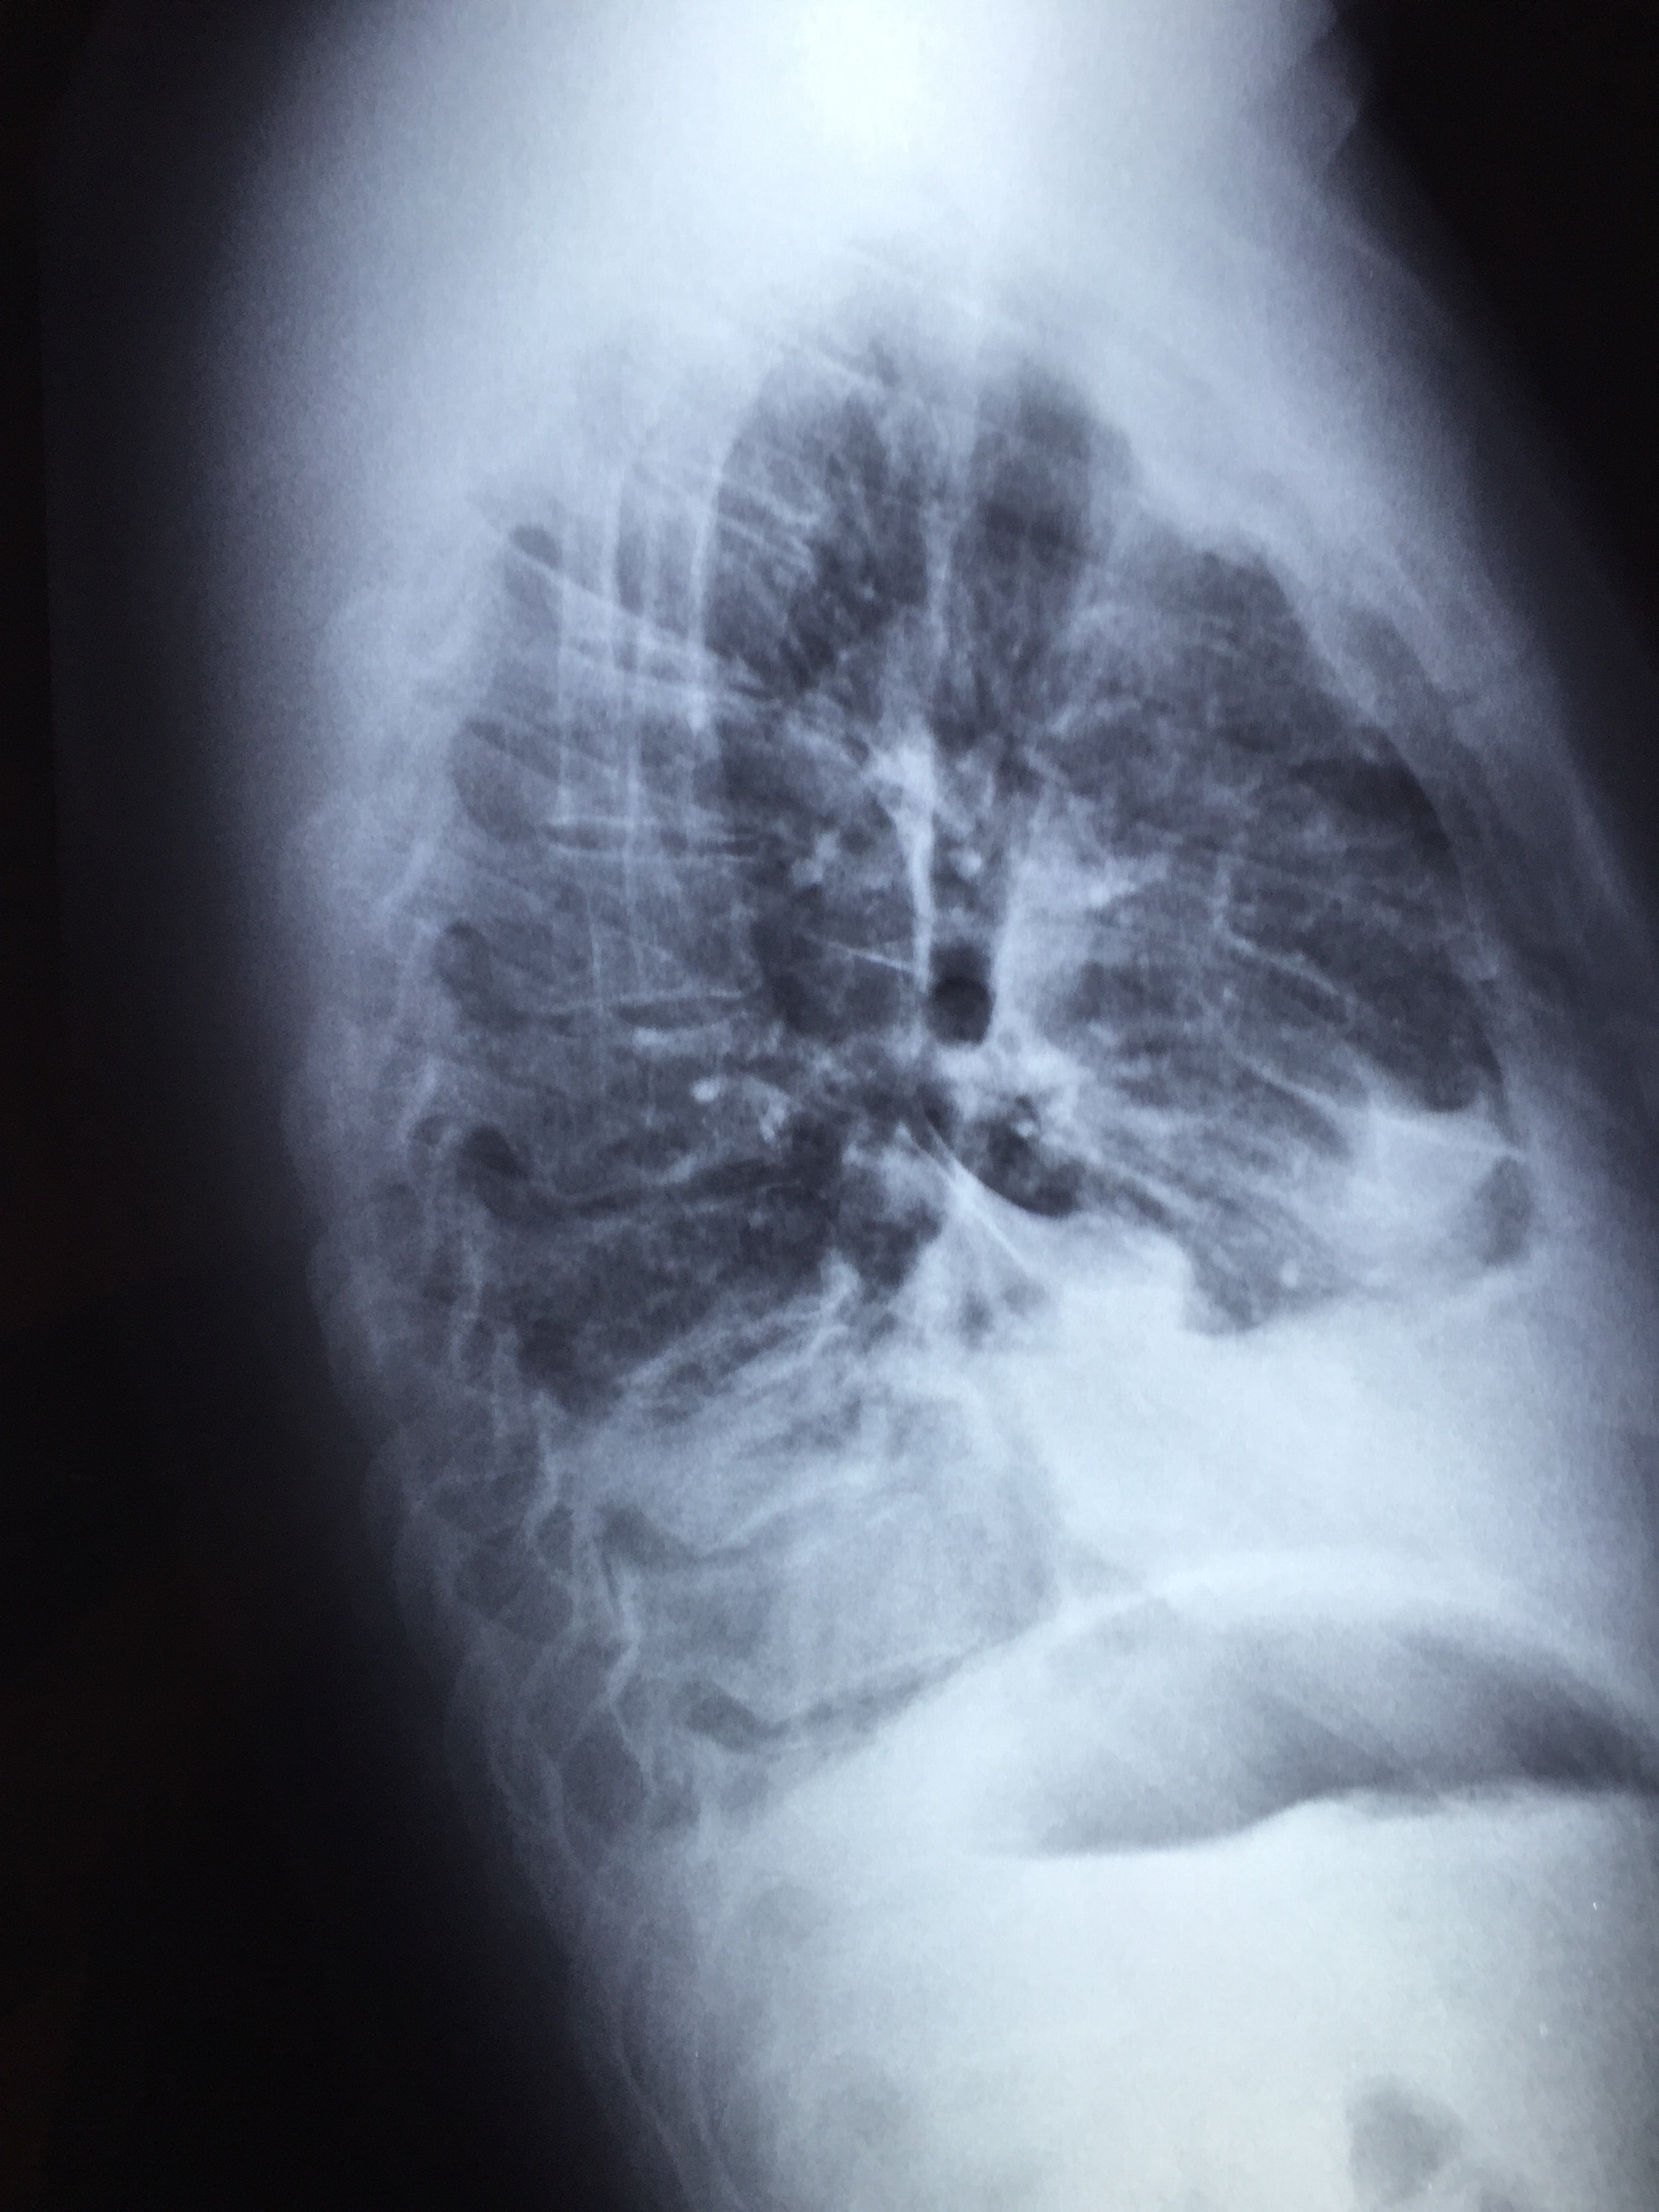

He was prescribed IV ceftriaxone but fever persisted. A day later, his blood cultures flagged positive for MRSA and he was switched to IV daptomycin. A transthoracic 2D-echo showed a normal heart with no evidence of endocarditis. His fever subsided after 2 days of daptomycin and he felt subjectively better. However, on the third day of daptomycin therapy, he experienced right chest wall pain and slight breathlessness on walking to the bathroom. This failed to resolve with symptomatic treatment and chest X-rays were ordered.

One of daptomycin’s unique and less desirable features is that the drug is broken down by lung surfactant, and hence it is inadequate for the treatment of pneumonia. In this particular case, the most likely scenario is a subclinical MRSA pneumonia that worsened even as the patient responded systematically to daptomycin, resulting in clinical pneumonia with parapneumonic effusion (an empyema cannot be completely ruled out at this stage as well, but is unlikely as daptomycin penetrates the pleura in adequate concentrations). He was switched to oral linezolid and recovered without any issues.